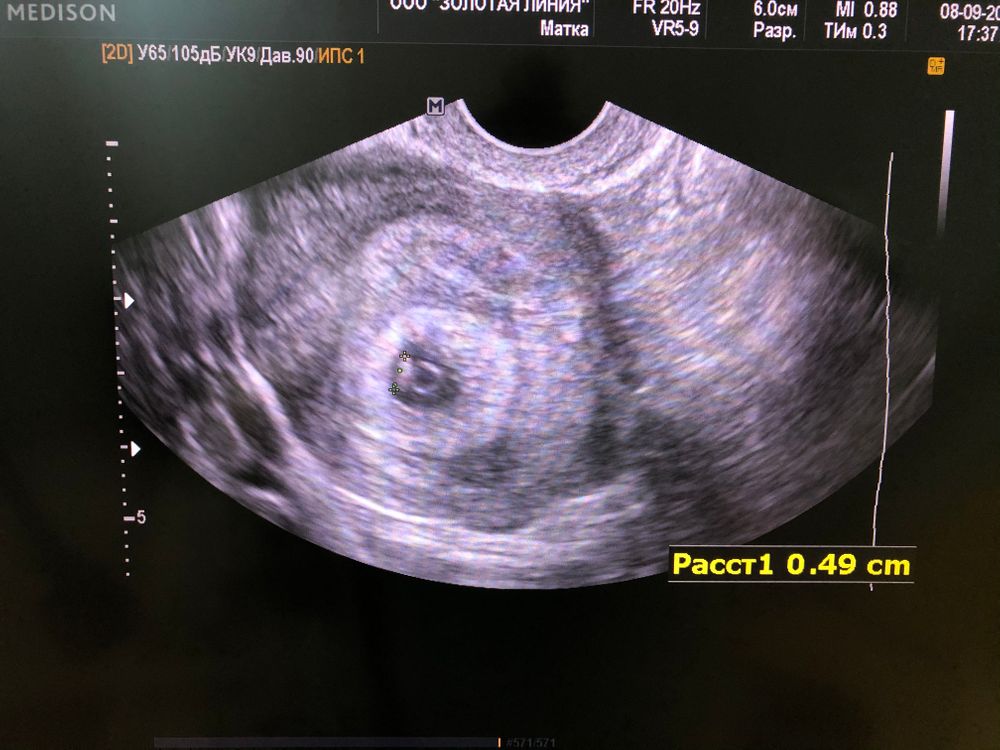

Вот мое долгожданное бриллиантовое кольцо🥰 по УЗИ 5,5 нед, по ПМ 6,6нед🙏🏻

Sinichka, да) круглое это желточный мешочек, а бриллиантик малыш)🌸

Люси, в след узи приду, через 2 недели записалась) там уже и ручки и ножки она сказала будут и сердечко послушаем) в 7,5 недель) сейчас на мониторе движение еле заметное она нашла (сердцебиение), но пока он маленький сильно🥰 мне самое главное, что за недельку он появился и подрос🙏🏻 я верю, что все хорошо и сердечко будет биться❤️ спасибо вам)🙏🏻 Тебе тоже легкой беременности)